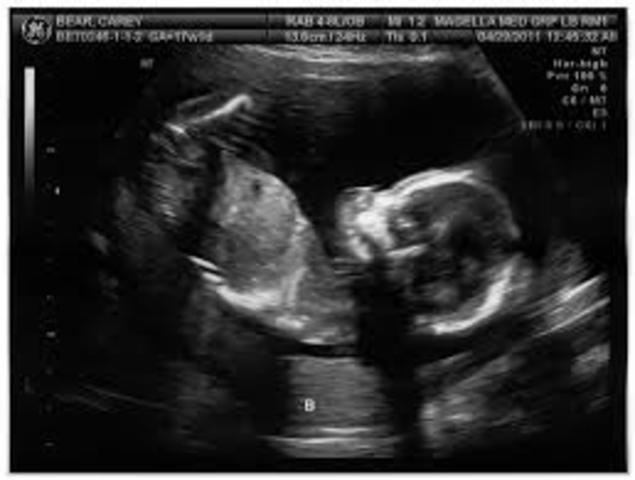

• Pregnancy at 13 & 14 weeks

Pregnancy at 13 & 14 weeks

Baby's organs now fully formed. Everything is growing really fast right now, by the end of the trimester, baby will be doubled in size. The baby is growing and growing. Baby is almost fully formed but it weighs under two ounces. Baby is producing its own hormones.